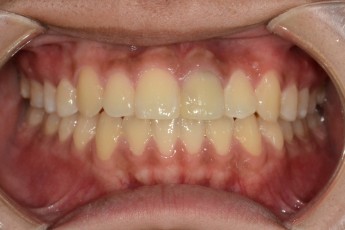

- 매복치교정